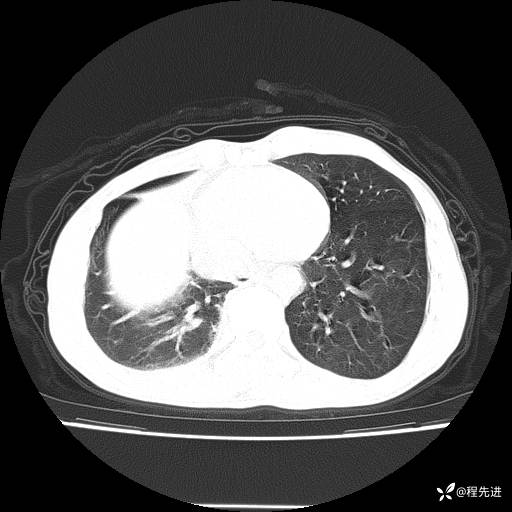

患者性别:男

患者年龄:49岁

主诉:咳嗽、胸痛1周

简要病史:1周前受凉感冒后开始出现咳嗽症状,阵发性连声咳,痰多,黄白痰,不易咳出,伴胸痛、气紧、胸闷,右侧为主,活动用力、呼吸时胸痛明显,曾在当地诊所贴敷膏药仍疼痛

体格检查:T:36.3 ℃ P:80 次/分 R:20 次/分 BP:120/88 mmHg,指脉氧饱和度97%,意识清晰,呼吸平稳,右侧第二、三肋骨压痛,可见膏药贴敷,皮肤无异常,双肺呼吸音粗,未闻及干湿性啰音。心率80次/分,节律整齐,无杂音。腹平软,全腹无压痛无反跳痛

临床诊断:社区获得性肺炎

CT平扫: